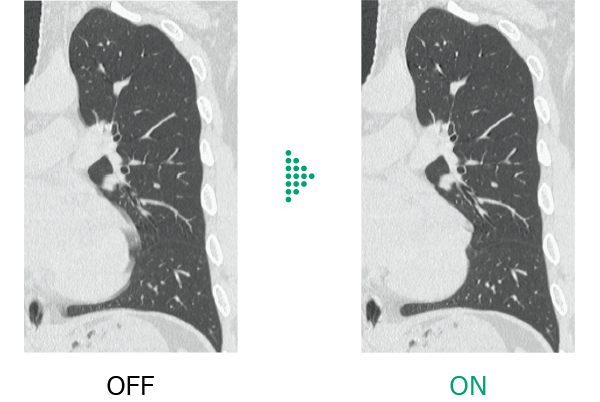

Conventional chest CT scans*1 have faced challenges due to motion artifacts caused by heartbeat and patient motion , making diagnosis difficult in some cases.

Body StillShot*2 calculates the direction and amount of patient motion in four dimensions from the collected raw data, providing images with minimal blurring caused by motion . It can also be used in combination with Intelli IPV*3 , an image reconstruction technology developed using AI, contributing to further image quality improvement.